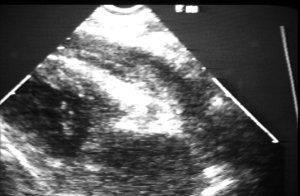

It all began in 1984, when EM faculty physician Dr. Ray Mayron obtained an ultrasound machine from Dr. Richard Asinger in the Department of Cardiology, for use on evenings and weekends (Photo 1). The machine shown in Photo 1 has a Sony Rear projection cathode ray TV balanced on top of the control panel and a VCR on the right. This machine met its death after a positive examination when a life-threatening condition was diagnosed and required rapid action and it was pushed away and fell over. Dr. Mayron was initially investigating the use of ultrasound for diagnosing cardiac and pericardial abnormalities such as hemopericardium (see Photo 2) and pericardial tamponade, which was the cause of life-threatening obstructive shock in the patient treated by Drs. Wyatt and Haug.